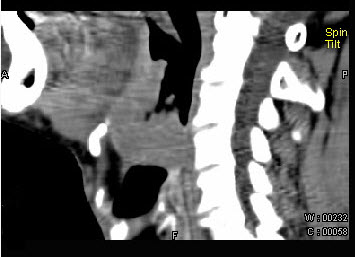

男,74岁,咽喉部不适一年余,近两三个月咽喉疼痛,吞咽困难,CT如图所示,最可能诊断是()。

A、喉癌

B、会厌癌

C、声带癌

D、声门下区癌

E、跨声门型癌

正确答案:

B